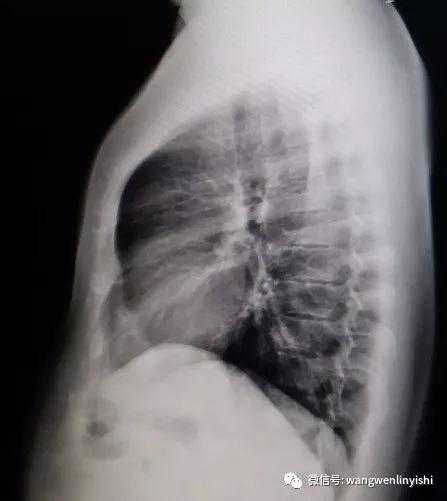

The upper part of the patient’s chest wall is protruded as a whole, coupled with depressions in the central and lower regions, presenting a classic example of Wenlin chest.

The Specificity of Wenlin Chest

Wenlin chest is a distinctive chest wall deformity that was often mistakenly identified as pectus carinatum in the past. However, unlike PC, which is characterized by a single protrusion, Wenlin chest involves both protrusions and depressions, classifying it as a kind of complex chest wall deformities. This malformation can not be corrected by traditional surgeries that work for PC. Notably, the depression in Wenlin chest is only apparent in comparison to the protrusion of the upper chest wall, without significantly compressing the patient’s heart.